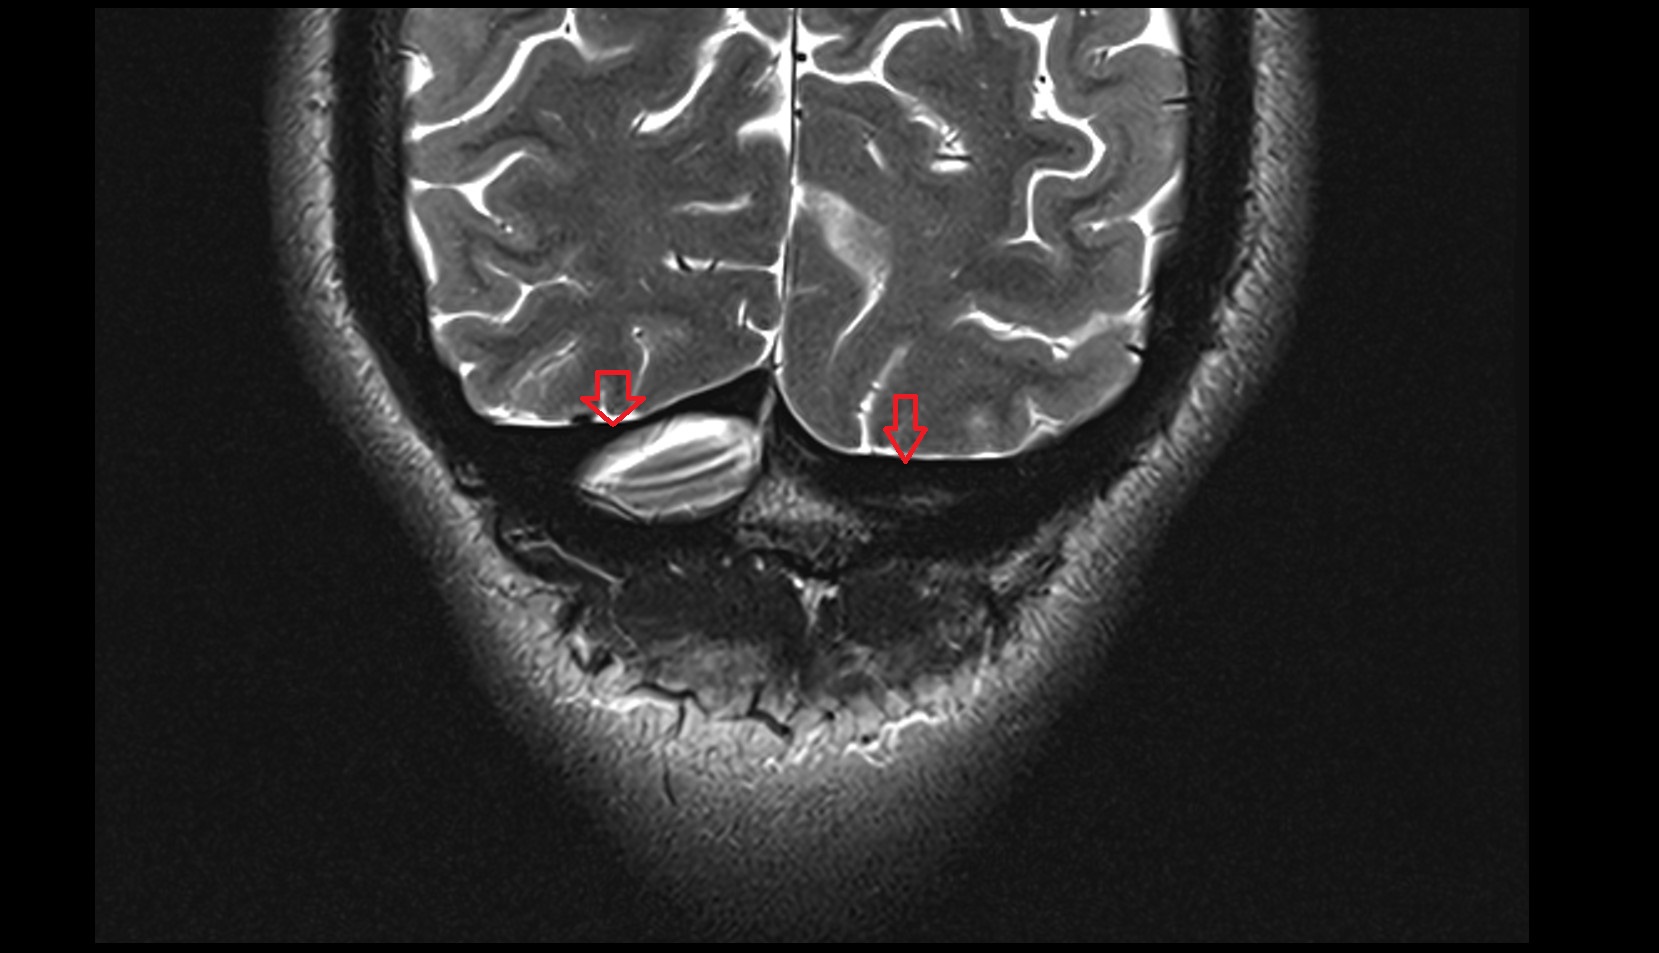

- Hippocampal head

- Head of hippocampus